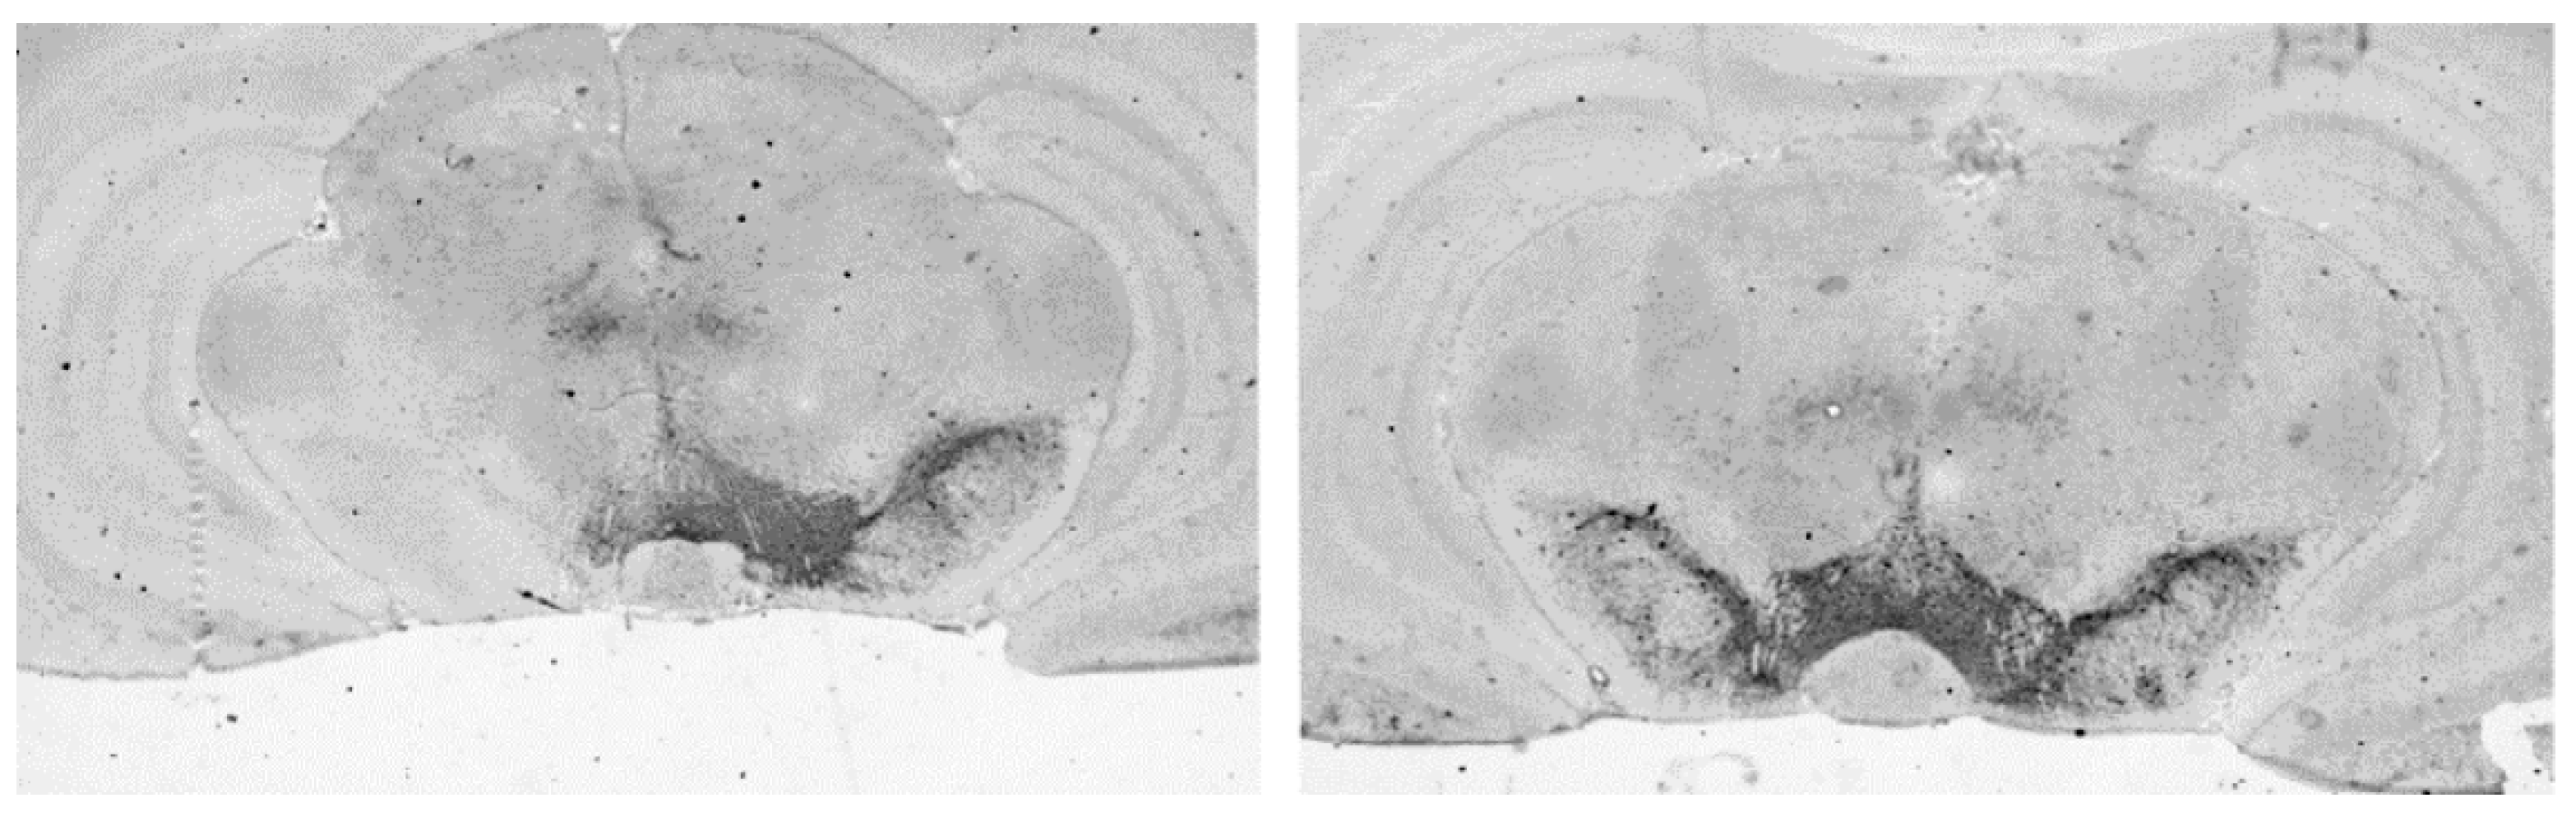

3.4.1. Loss of Dopaminergic Neurons in SN

| Treatment Group | Percentage of Neuron Loss in SN ( ± SD) | n |

|---|---|---|

| E2+L-dopa | 88.7 ± 5.8 | 15 |

| L-dopa | 89.9 ± 6.2 | 10 |

| E2+saline | 91.7 ± 6.6 | 12 |

| Saline | 87.6 ± 6.3 | 13 |